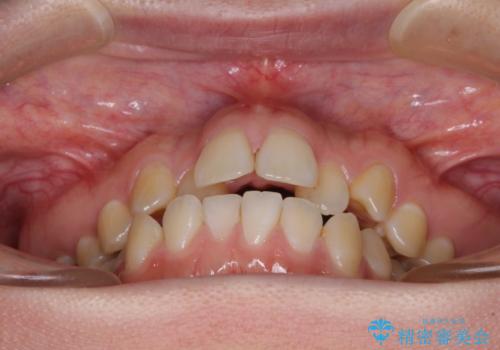

- 前歯のデコボコを気にして来院された患者様です。

前歯のデコボコはもちろん気になるところですが、舌の突出癖により上下前歯が非接触となっている状態でした。

上下前歯が非接触である開咬は、インビザラインによる治療がお勧めではありますが、しっかりと使う自信がないとのことで、ワイヤー装置にて治療を行うこととしました。